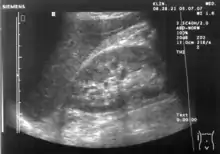

Liver

Liver: Diffusely homogeneous and normal in echogenicity. No focal mass or contour nodularity. No intrahepatic biliary ductal dilatation.